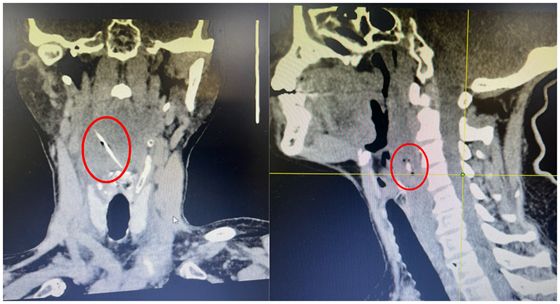

当地医院后行CT检查时发现,鱼刺已进入咽后间隙,即鱼刺穿破黏膜进入更深层组织里——鱼刺“躲起来”了!当地医院评估风险较高,建议转上级医院就诊。患者因疼痛加重并颈部活动受限,遂来我院耳鼻咽喉头颈外科就诊,检查后发现鱼刺完整进入咽后间隙合并感染,大体位于下咽平面,离颈椎体仅0.7公分。

CT影响显示鱼刺进入咽后间隙

术中可见鱼骨周围肉芽组织增生,出血量不足5毫升,术后完整取出长约3.7公分鱼骨